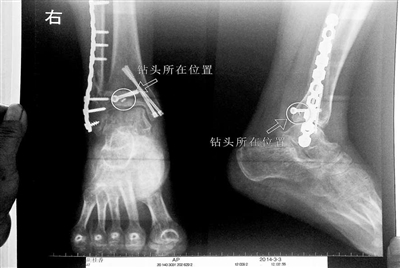

胡女士的腿部X光圖

看著X光片中自己腿內(nèi)的異物,胡女士就感到莫名的擔(dān)憂。胡女士于2013年3月在北京市豐臺(tái)區(qū)右安門(mén)醫(yī)院進(jìn)行了一次骨折手術(shù),術(shù)后醫(yī)生才發(fā)現(xiàn)手術(shù)時(shí)用來(lái)打眼用的鉆頭不慎遺留在了胡女士的骨頭中,并且無(wú)法取出。

近日,在豐臺(tái)區(qū)右安門(mén)醫(yī)院,北京青年報(bào)記者見(jiàn)到了胡女士,她走起路來(lái)顯得一瘸一拐,腿腳并不利索。在她帶來(lái)的X光片上,可以清晰地看到,有一個(gè)異物存在于腿內(nèi)部。

“我當(dāng)時(shí)就嚇蒙了,怎么會(huì)有一個(gè)鉆頭在骨頭里?”胡女士余悸未消地說(shuō),第二天拍攝的X光片顯示,2厘米左右的鉆頭遺留在她右腳腳踝上部的骨頭內(nèi)。

胡女士說(shuō),當(dāng)時(shí)旁邊的醫(yī)生勸慰自己,稱鉆頭留在腿里并不會(huì)有什么問(wèn)題。出院后,胡女士每個(gè)月都會(huì)來(lái)醫(yī)院做復(fù)查,拍X光片。她說(shuō),每次都能夠清晰地看見(jiàn)自己骨頭里的那個(gè)明晃晃的“小東西”。